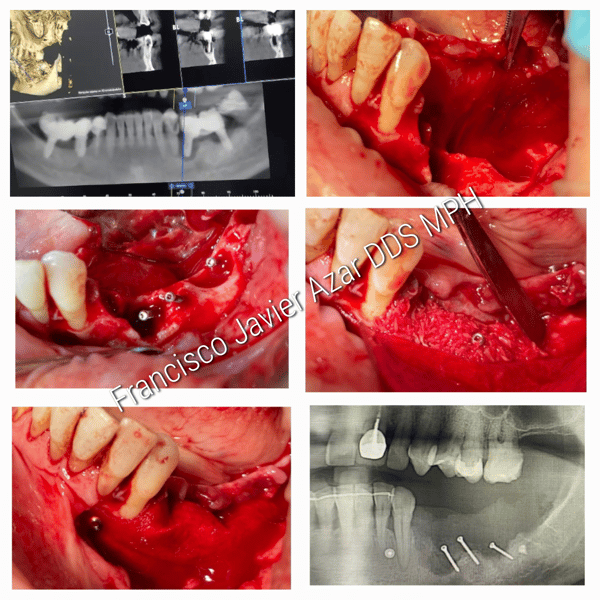

The patient presented with a poorly healed site with previously failed dental implants. An aggressive guided bone regeneration procedure was indicated, using a combination of DALI Grafts, including, DALI Amnion Chorion Membranes, to facilitate bone growth for future implant placement.